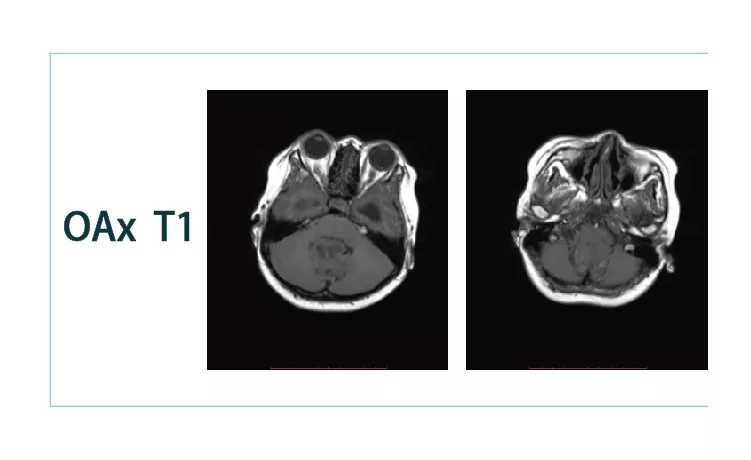

【朗润影像档案】20181026磁共振影像病例结果讨论